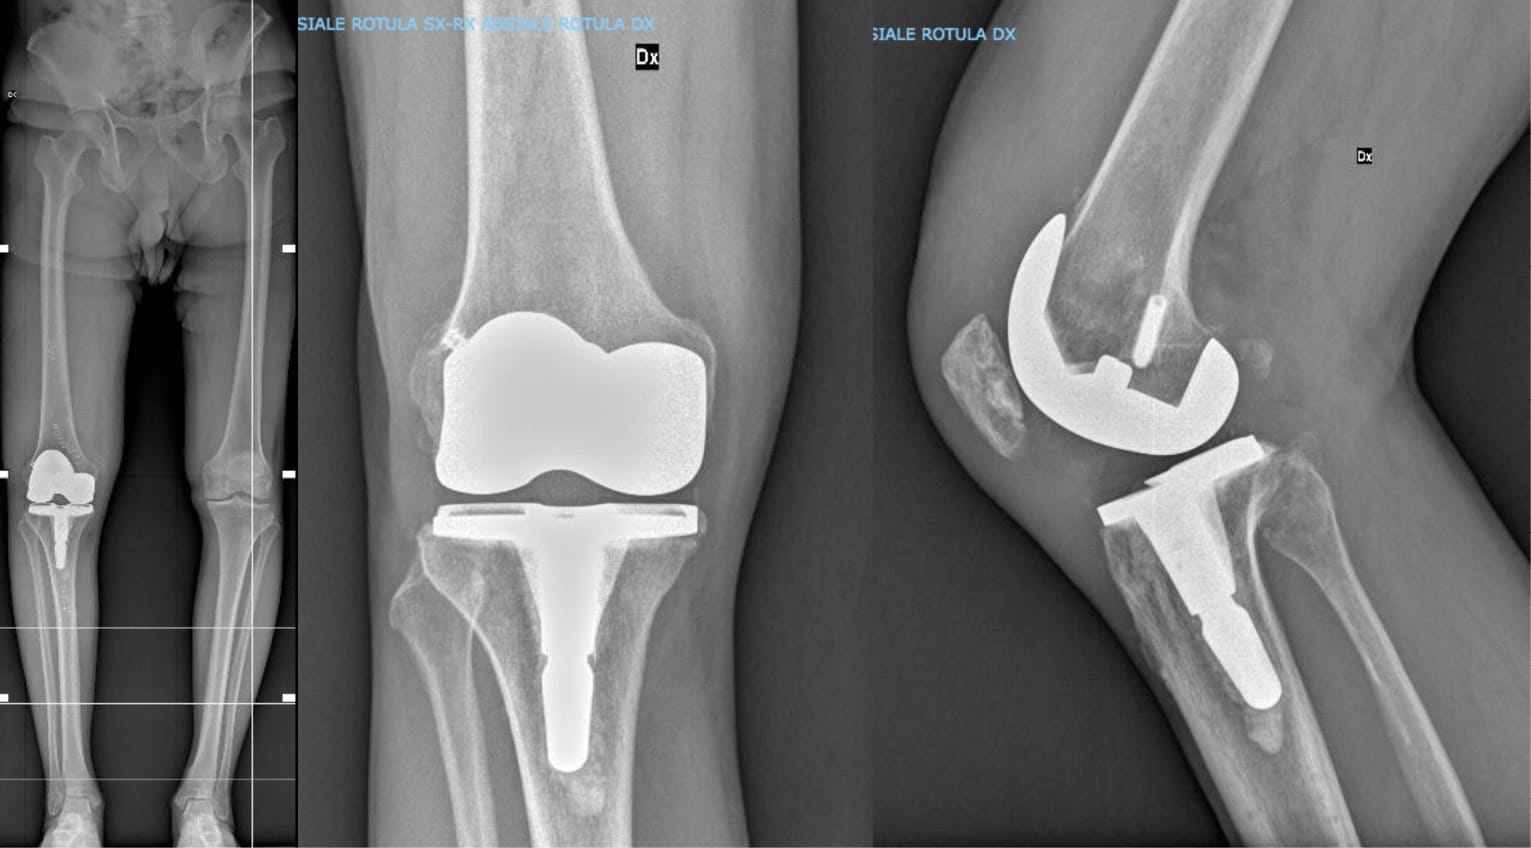

All patients underwent surgery using the same technique, following an individualized alignment approach, as described by Rossi and Benazzo [14] Rossi SMP, Benazzo F. Individualized alignment and ligament balancing technique with the ROSA® robotic system for total knee arthroplasty. Int Orthop 2023;47:755–62. https://doi.org/10.1007/s00264-022-05671-z.. According to the defined parameters, this technique is based on initial planning of intra-articular corrections with bone resections, followed by a tibial resection, which allows for validation and data implementation in the planning. Next, a re-evaluation of ligament compliance is performed using the FuZion tensioning device (Zimmer Biomet, Warsaw, IN, USA), followed by a distal femoral resection, executed based on ligament constraints after the tibial cut. Finally, FuZion is used for final rotational alignment, and the procedure is completed with 4-in-1 femoral cuts, tibial and patellar preparation, and cementing (Figure 2).

For standard implants, the Persona® (Zimmer Biomet, Warsaw, IN, USA) was used, while for Varus-Valgus Constrained (VVC) implants, the NexGen® Legacy® Constrained Condylar Knee (LCCK, Zimmer Biomet, Warsaw, IN, USA) was utilized.

No patient required an osteotomy of the anterior tibial tuberosity due to reduced flexion and/or a low patella. Additionally, no patients required the use of cones or tibial augments, and no in-hospital complications were recorded in either group. Fixation devices were completely removed at the femoral level in 8 patients (22.9%), while they were left in place in 20 patients (57.1%). The remaining 7 patients (20%) exhibited resorption of the fixation devices (Figure 3).

At the tibial level, fixation devices were removed in 18 patients (51.4%), either not removed or only partially removed in 10 patients (28.6%), while 7 patients (20%) exhibited resorption of the fixation devices.